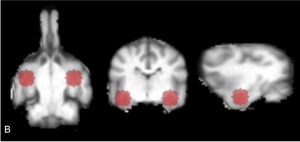

The study used noninvasive fMRI brain imaging to measure activity in the amygdala of dogs upon exposure to a human-dog social situation where the dog’s caregiver provided attention to another dog. No previous study neuroscientifically showed the exhibition of canine jealousy.

The premise of the experiment was that if the dogs exhibited jealousy, we should observe jealousy in Condition 2, since a “rival dog” was receiving the owner’s attention and the food treat. Condition 3 was a control condition to measure the amount of activity relevant solely to the loss of owner attention and the food treat, in contrast to the loss of such to a conspecific rival. Therefore, evidence of jealousy will result when there is greater amygdala activation in Condition 2 in comparison to Condition 3.

Upon the conclusion of each dog’s fMRI session, the data was pre-processed for motion correction, censoring, and normalization and then analyzed using ANTS, AFNI, and SPSS software. The results showed a significant correlation between amygdala activity and the C-BARQ dog-directed aggression score, whereby dogs with a history of aggression to conspecifics had higher amygdala activation during the initial fake dog trials. However, as the experiment progressed the dogs habituated, whereupon amygdala activity gradually diminished.